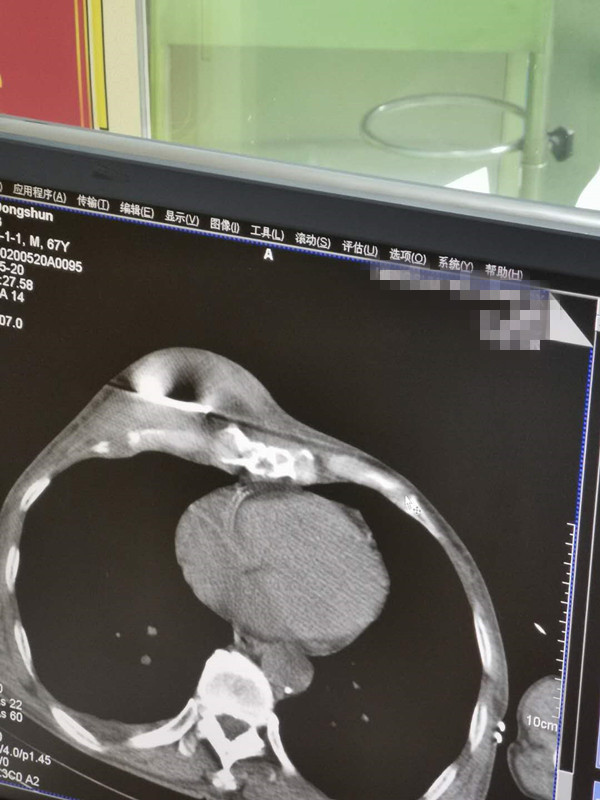

67岁胸部肉瘤氩氦刀冷冻消融

发布人:美国氩氦刀技术官方网站    发布时间:2020/5/21 14:53:37